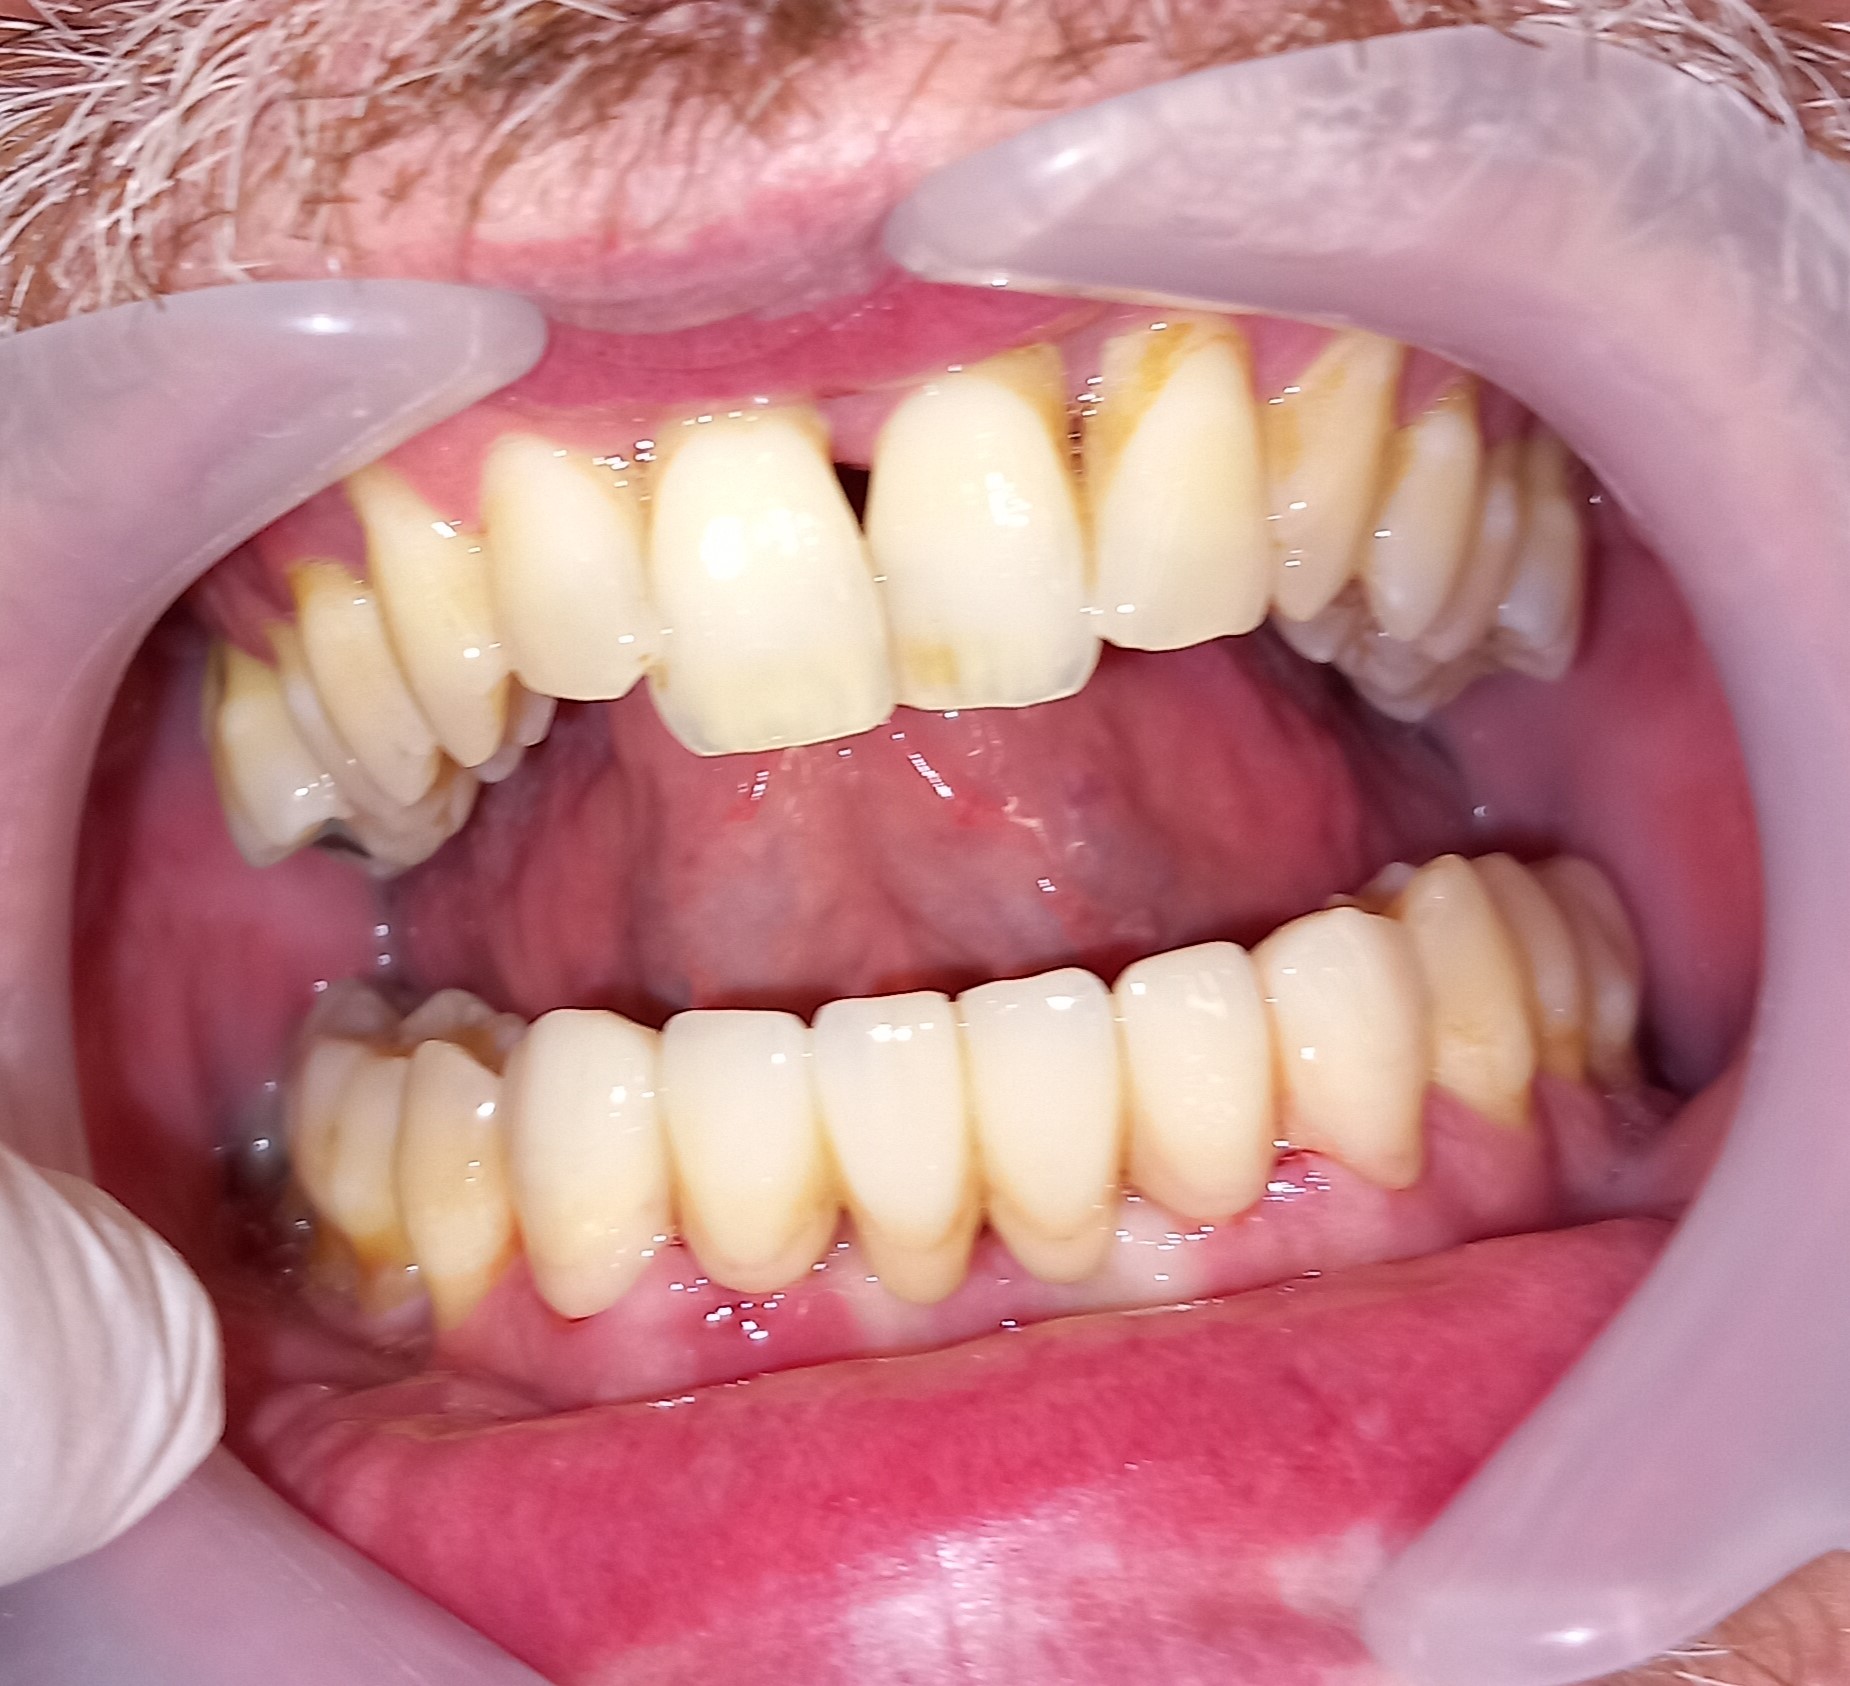

Ο ασθενής δεν είναι ευχαριστημένος με την αισθητική των 6 άνω πρόσθιων δοντιών. Επιπρόσθετα αυτά τα δόντια είχαν παλιές μεγάλες ανασυστάσεις, οι οποίες είχαν επανατερηδονιστεί. Για όλους τους ανωτέρους λόγους αποφασίστηκε, μετά από την απαραίτητη συζήτηση με τον ασθενή η αποκατάσταση των δοντιών με ολοκεραμικές θήκες. Τα δόντια τροχίστηκαν, αντικαταστάθηκαν οι παλιές εμφράξεις των δοντιών και στη συνέχεια λήφθηκαν αποτυπώματα, τα οποία στάλθηκαν στον οδοντοτεχνίτη. Σε όλη τη διάρκεια, που ο οδοντοτεχνίτης κατασκεύαζε τις νέες προσθετικές αποκαταστάσεις ο ασθενής φορούσε προσωρινές θήκες, οι οποίες είχαν ικανοποιητική αισθητική εμφάνιση.

Είναι σημαντικό να τονιστεί οτι ο ασθενής επιθυμούσε οι θήκες των 6 άνω πρόσθιων δοντιών να είναι αισθητά λευκές, παρόλο που διέφεραν χρωματικά από τα υπόλοιπα δόντια.

Ο ασθενής είναι ευχαριστημένος τόσο με την αισθητική όσο και με τη λειτουργία των νέων προσθετικών αποκαταστάσεων.

Αρχική κλινική εικόνα των 6 άνω πρόσθιων δοντιών

Προσωρινή αποκατάσταση των 6 άνω πρόσθιων δοντιών

Τελική κλινική εικόνα των 6 άνω πρόσθιων δοντιών